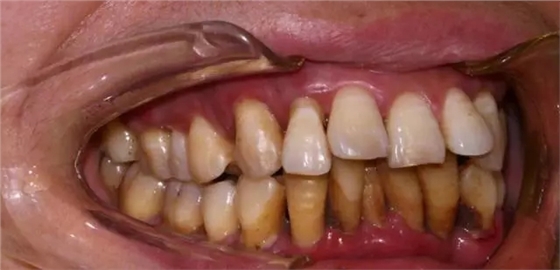

治療前頰側:牙周紅腫、牙周溢膿,大量牙石

治療前腭側:牙周紅腫、牙齦呈現(xiàn)暗紅色

治療起來是非常艱難的,牙齒根面布滿了牙石,牙齒又搖搖晃晃,牙周紅腫溢膿,該如果治療?